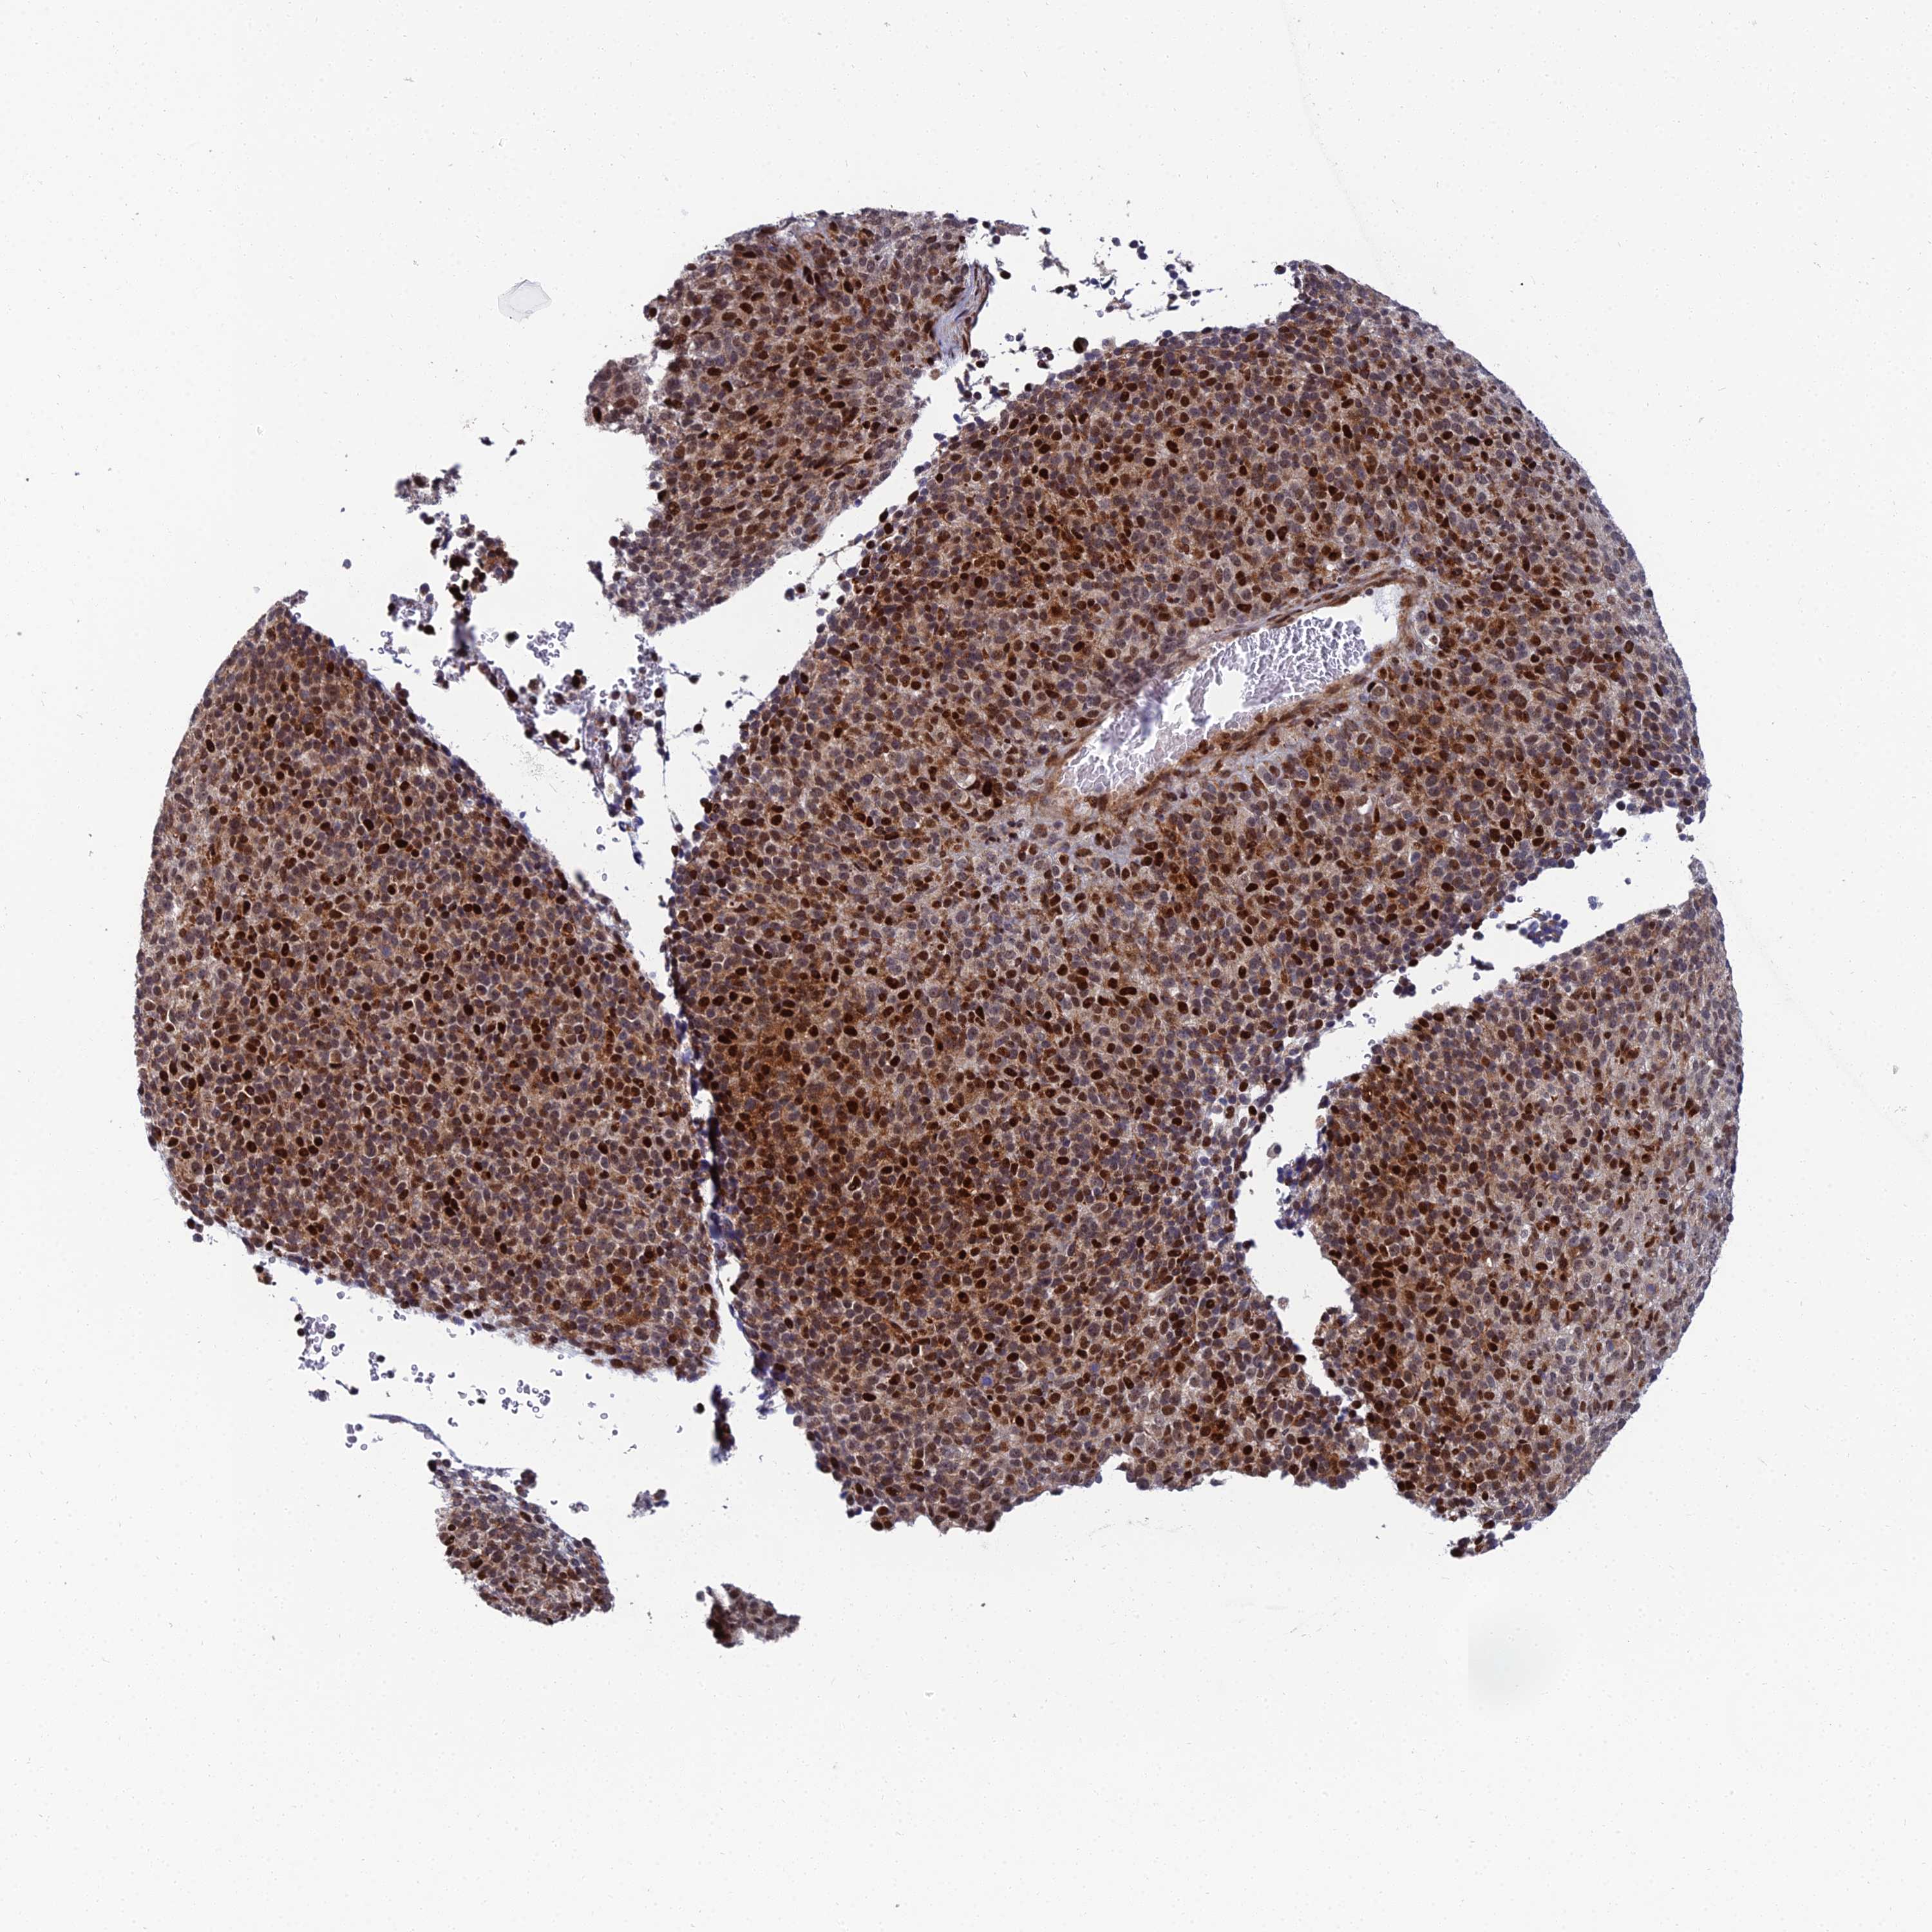

MELANOMA - Protein expressioni

A mouse-over function shows sample information and annotation data. Click on an image to view it in a full screen mode. Samples can be filtered based on level of antibody staining by selecting one or several of the following categories: high, medium, low and not detected. The assay and annotation is described here.

Note that samples used for immunohistochemistry by the Human Protein Atlas do not correspond to samples in the TCGA dataset.

Antibody stainingi

Antibody staining in the annotated cell types in the current human tissue is reported as not detected, low, medium, or high, based on conventional immunohistochemistry profiling in selected tissues. This score is based on the combination of the staining intensity and fraction of stained cells.

Each image is clickable and will lead to virtual microscopy that enables deeper exploration of all samples and also displays staining intensity scores, fraction scores and subcellular localization as well as patient and tissue information for each sample.

Antibody HPA043048

Staining

High

Medium

Low

Not detected

Intensity

Strong

Moderate

Weak

Negative

Quantity

>75%

75%-25%

<25%

None

Location

Nuclear

Cytoplasmic/membranous

Cytoplasmic/membranous,nuclear

Malignant melanoma, NOS

Malignant melanoma, Metastatic site